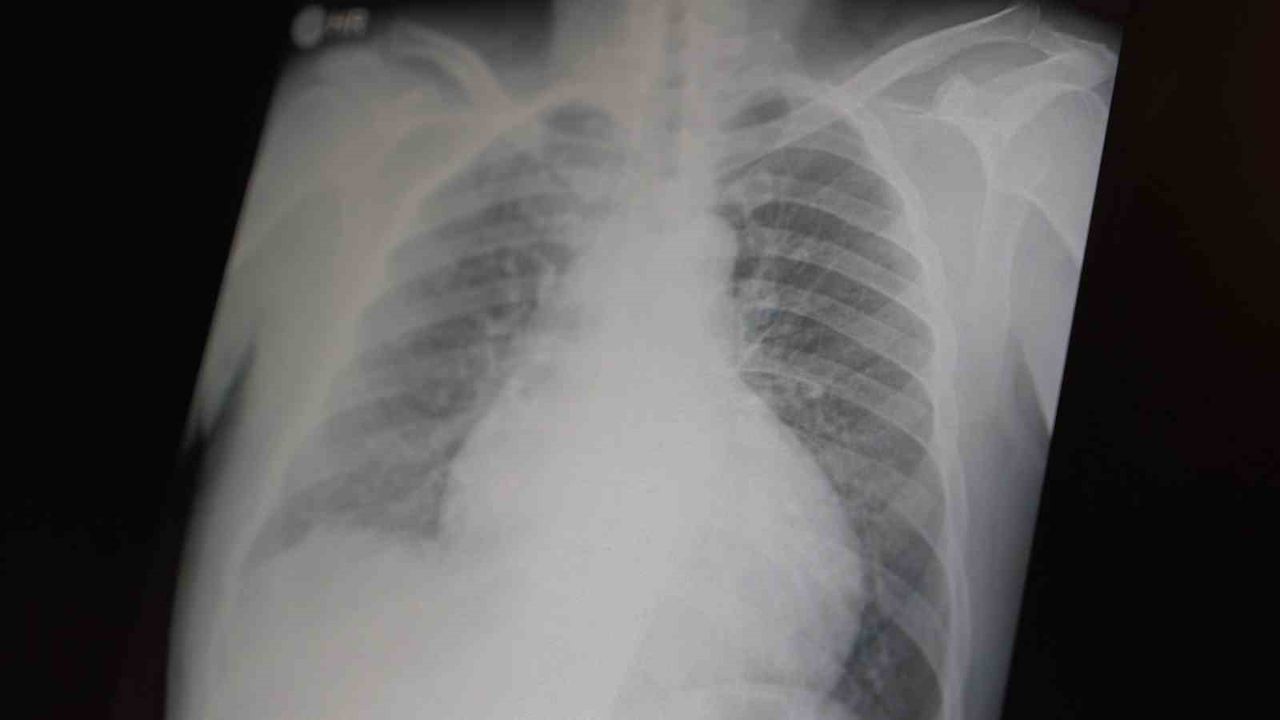

Prof. Dr. Şevket Özkaya, çocukları ve gençleri etkileyen bağımlılıklar hakkında açıklamalarda bulundu. Metamfetaminin sentetik bir madde olduğunu ve kullanımının ölümcül sonuçlar doğurduğunu ifade eden Özkaya, "Tüm dünyada çocukları ve gençleri etkileyen iki önemli bağımlılıktan bahsetmek istiyorum. Bunlar metamfetamin ve kokain bağımlılığıdır. Metamfetamin en ölümcül, en çok bağımlılık yapan, okul çağında en kolay ulaşılabilen bir sentetik maddedir. Kullanıma bağlı ciddi akciğer ve karaciğer sorunları ortaya çıkıyor. Çok küçük dozlarda bile anında bağımlılık yapabiliyor ve tedaviyle bırakılması çok zor bir bağımlılıktır" dedi.

Açıklamalarında, her iki maddenin beyin hasarı oluşturduğunu ve nöro sinir hücrelerini harap ederek solunum ve kalbin durmasına sebep olduğunu vurgulayan Özkaya, "Metamfetamin tüm dünyada bir sorun olmanın ötesinde, ülkemizde de gençlerimizi etkileyen toplumsal bir sorun olarak görülmelidir" ifadelerini kullandı.